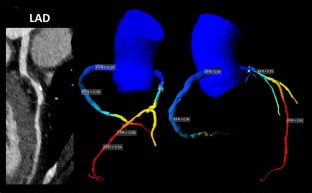

Fig. 2